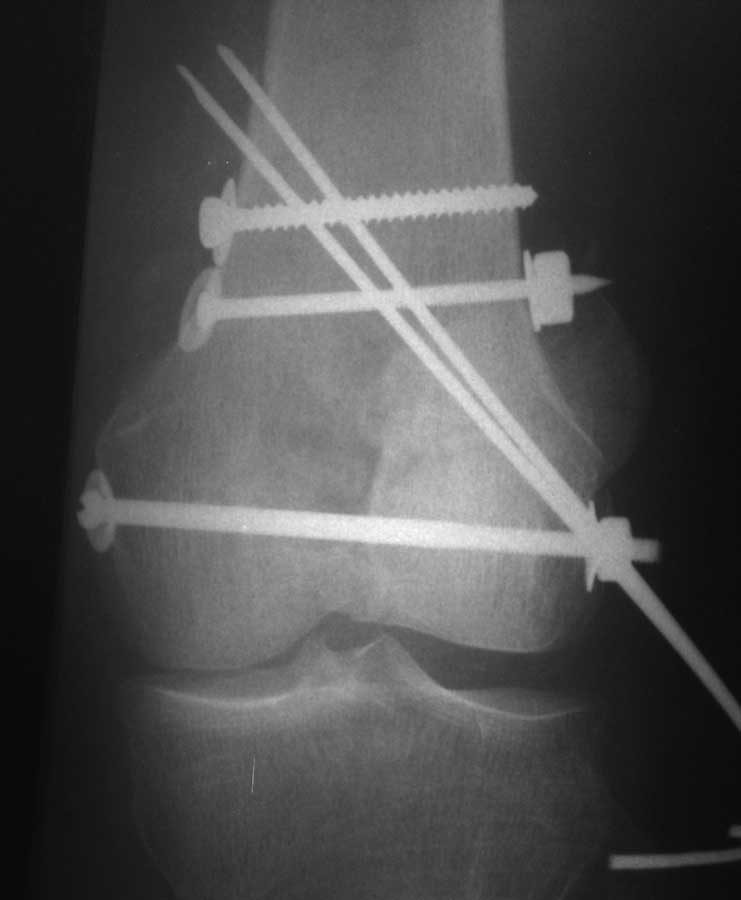

Коллеги, извиняюсь за задержку с результатом. Через медиальную артротомию обнажили н/3 бедра, отрепонировали внутренний мыщелок, затем по нему сопоставили суставную поверхность бедра с латеральным мыщелком.

По прямому снимку репозиция удалось, поздравляю! А с латеральной стороны подозрение на флексионный компонент латерального мыщелка остается, а снимок получился косым, надо было бы повторить.

Выбор имплантов не совсем удачный, подкожно выступающие болты в мыщелках вскоре могут привести к проблемам. Вместо солитарной фиксации болтом-стяжкой дистально можно было бы добавить пару винтов, которые создали бы ротационную стабильность и межфрагментарную компрессию.

Возможно, есть скрытый замысел, неочевидный для нас - не понятны латерально оставленные спицы. Спицы возможный очаг вторичного осложнения, и, тем более у взрослых, тонкие спицы не создают адекватную фиксацию.

Djoldas,скрытого смысла в спицах нет. Без них латеральный мыщелок получается фиксированным только к медиальному, который, в свою очередь, фиксирован к проксимальному отломку. Соответственно латеральный мыщелок не фиксирован к бедру. Спицами мы попытались создать какую-никакую-стабильность латерального мыщелка относительно проксимального отломка бедра.

Болт-стяжка, на мой взгляд, создает не меньшую межфрагментарную компрессию чем винты. Не понял относительно ротационной стабильности винтов.